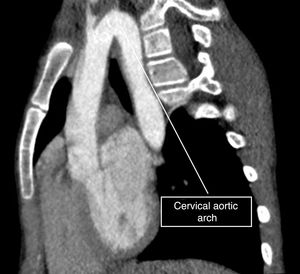

We present the case of a girl aged 9 years with DiGeorge syndrome referred to our hospital due to suspicion of right aortic arch. In the physical examination, the patient exhibited mild dyspnea, cough and occasional choking, with a palpable cervical pulse. The computed tomography (CT) scan of the heart revealed a complex vascular anomaly: a right-sided aortic arch extending cranially to the level of the right thoracic inlet, forming a cervical aortic arch (CAA) (Figs. 1 and 2, Appendix B video 1). The first branch of the aorta was the left common carotid artery, followed by the right subclavian artery, the left common carotid and the left subclavian artery (LSA). The LSA arose from a Kommerell diverticulum (Fig. 3, Appendix B video 2), which, combined with the ligamentum arteriosum, formed a complete vascular right that compressed the trachea (Fig. 3). Cervical aortic arch is an infrequent anomaly in the development of the aorta, occurring in fewer than 1 in 10 000 live births, characterized by an elongated aortic arch extending at or above the medial ends of the clavicles.1 This condition is associated with aneurysms (occurring in up to 20% of cases), coarctation of the aorta, congenital heart defects, Turner syndrome and DiGeorge syndrome.1,2 Given the presence of a complete vascular ring, surgery was the chosen treatment.3